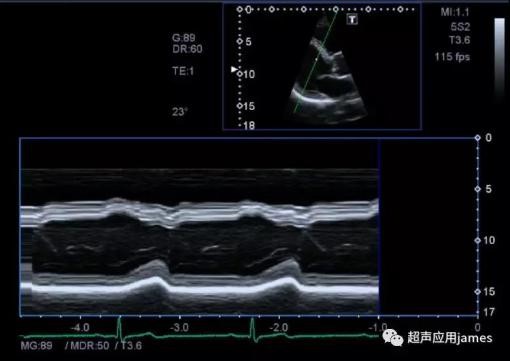

4.如果患者左心长轴和四腔心都很难获得较好的图像,影响心功能评估的时候,此时我们还可以利用频谱多普勒的方法获得左心室每搏量SV

5

6

采集步骤:获取三腔心或五腔心切面,取左室流出道血流频谱,进入心脏测量软件包,选择左室流出道VTI,测量射血期VTI值,测量左室流出道内径,获得左心室SV值。